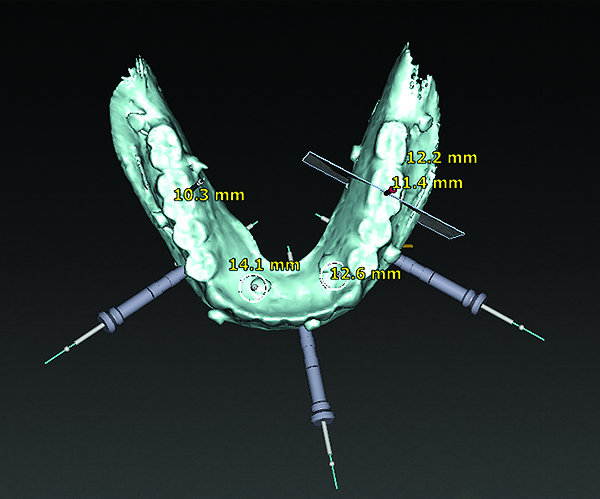

3D radiographic files (CT, CBCT) are stored digitally using a standardized digital imaging and communication in medicine (DICOM) format. In combination with a radiographic guide fabricated from a diagnostic wax-up, CBCT can be used to plan implant location and angulation based on prosthetically driven parameters and local bone/tissue constraints (Figure 8 through Figure 11). Currently, there are two different protocols to incorporate the radiographic guide in 3D scans and to perform computer guided surgery. The first is the double scan protocol, in which the patient wearing the radiographic guide and the radiographic guide alone are scanned separately. Fiduciary markers incorporated in the radiographic guide allow for matching of the two scans. This protocol allows for digitization of the surgical guide with great accuracy, irrespective of errors introduced by patient scans.18 Specialized software can be used to create a surgical guide (Figure 12).

3D radiographic scans obtained using the single scan protocol can be combined with digital mock-ups performed on intraoral optical scans or scans of casts,20 using the existing natural teeth as fiduciary markers. Different masks for bone, teeth, gingiva, and implants can be designated and processed (Figure 13 and Figure 14). This technology allows for greater accuracy, since implant position will be determined based on natural teeth (fiduciary markers) that are likely to be more stable and accurate than fiduciary markers placed on a radiographic guide.

(12) An example of a surgical guide produced using digital design and digital planning of implant position using the double scan protocol.

Figure 12